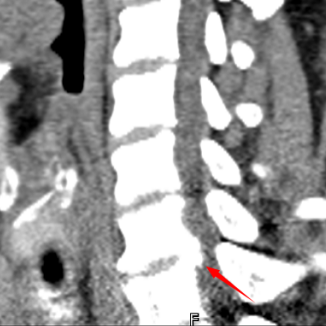

颈椎CT显示C6/7平面增生的骨赘占据椎管,压迫脊髓